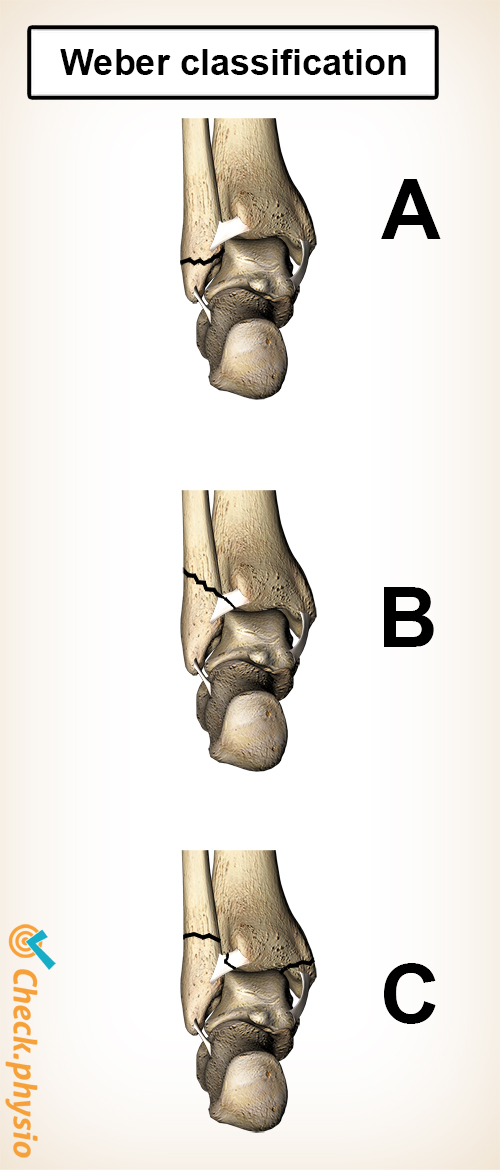

An ankle fracture is a break in one or more bones of the ankle. In many cases the calf bone breaks, but breaks can also occur in other parts of the ankle. In severe cases, bones will break in various places at the same time.